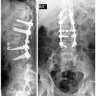

Upload Date: March 31, 2019 Full Size Image Dimensions: 358 × 400 Image Parent Post: Χειρουργική αντιμετώπιση καταγμάτων

3.Οπίσθια σπονδυλοδεσία για κάταγμα οσφυικού σπονδύλου